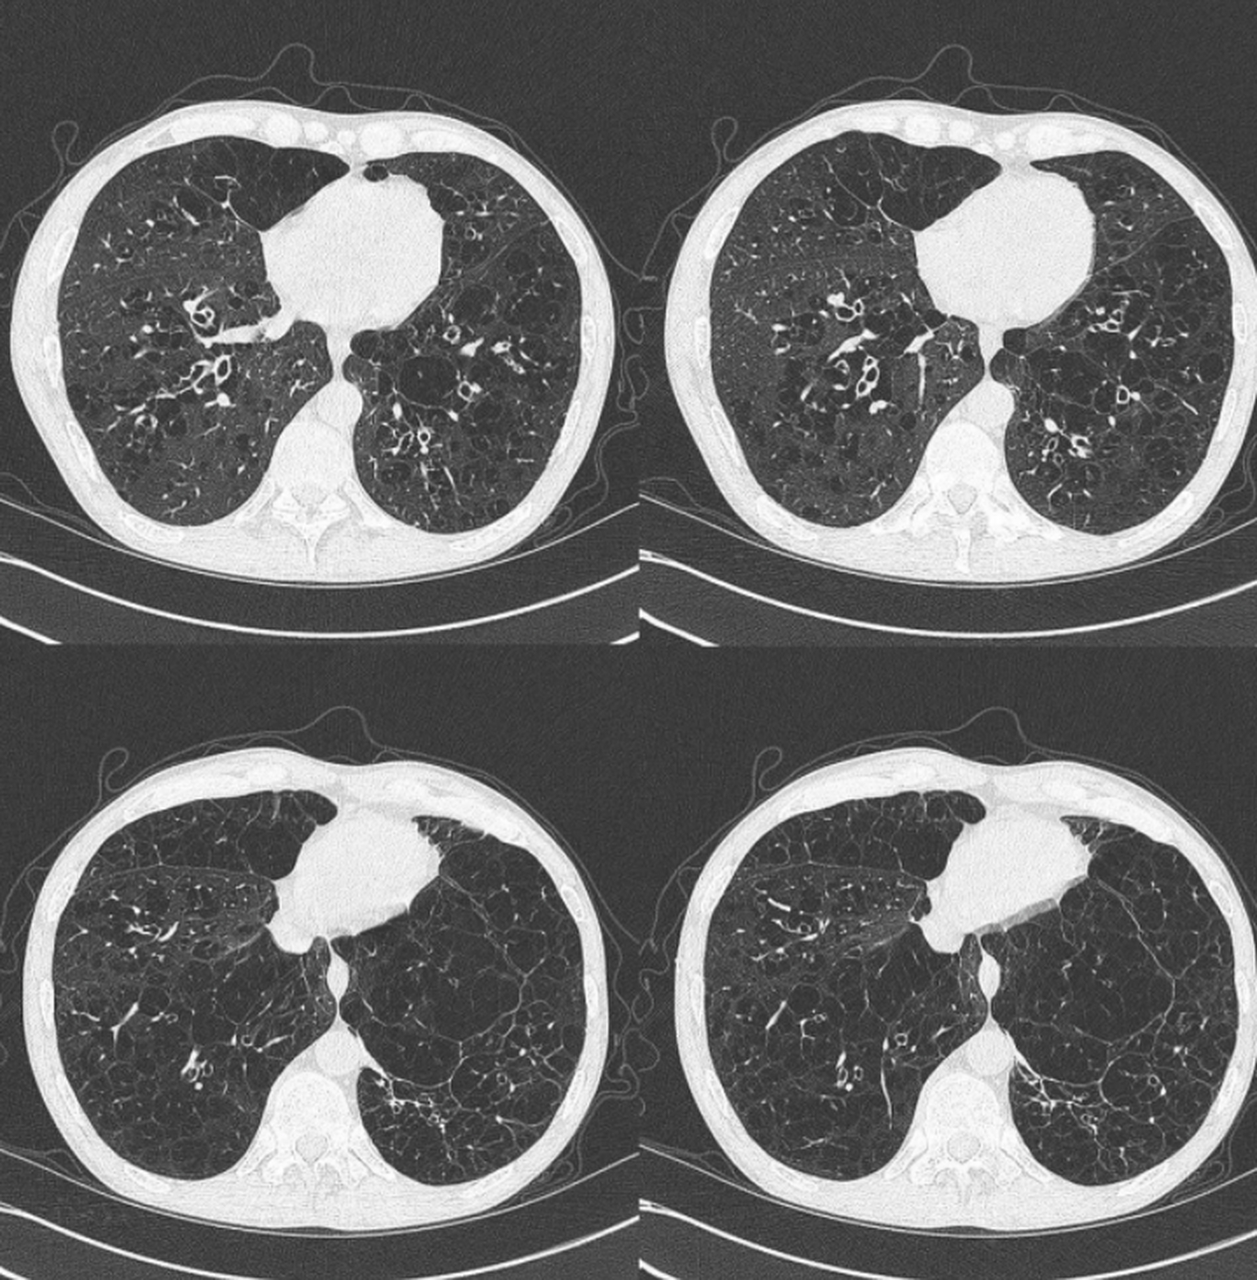

慢阻肺背景下的肺炎

慢阻肺,在肺ct上能看出来吗?